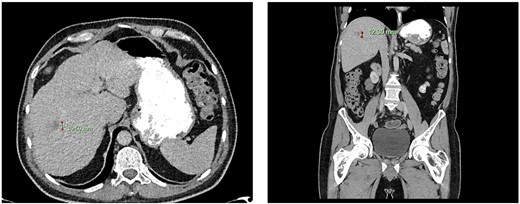

Computed tomography dated 15 January 2013 of the abdomen and pelvis measuring 10.50 mm (anterior–posterior) lesion at liver segment 5/6 in axial (left) and coronal (right) view.

Subsequent surveillance imaging including magnetic resonance imaging and CT scans demonstrated gradual reduction and eventual complete resolution of the liver metastases (refer to Figs 1–4). Furthermore, routine colonoscopy and a positron emission tomography (PET) scan revealed no evidence of locoregional cancer recurrence nor distant metastatic disease present; essentially rendering the patient cured from an initial diagnosis of metastatic rectal cancer. It has been at least a decade since his initial diagnosis and the patient remains in remission.